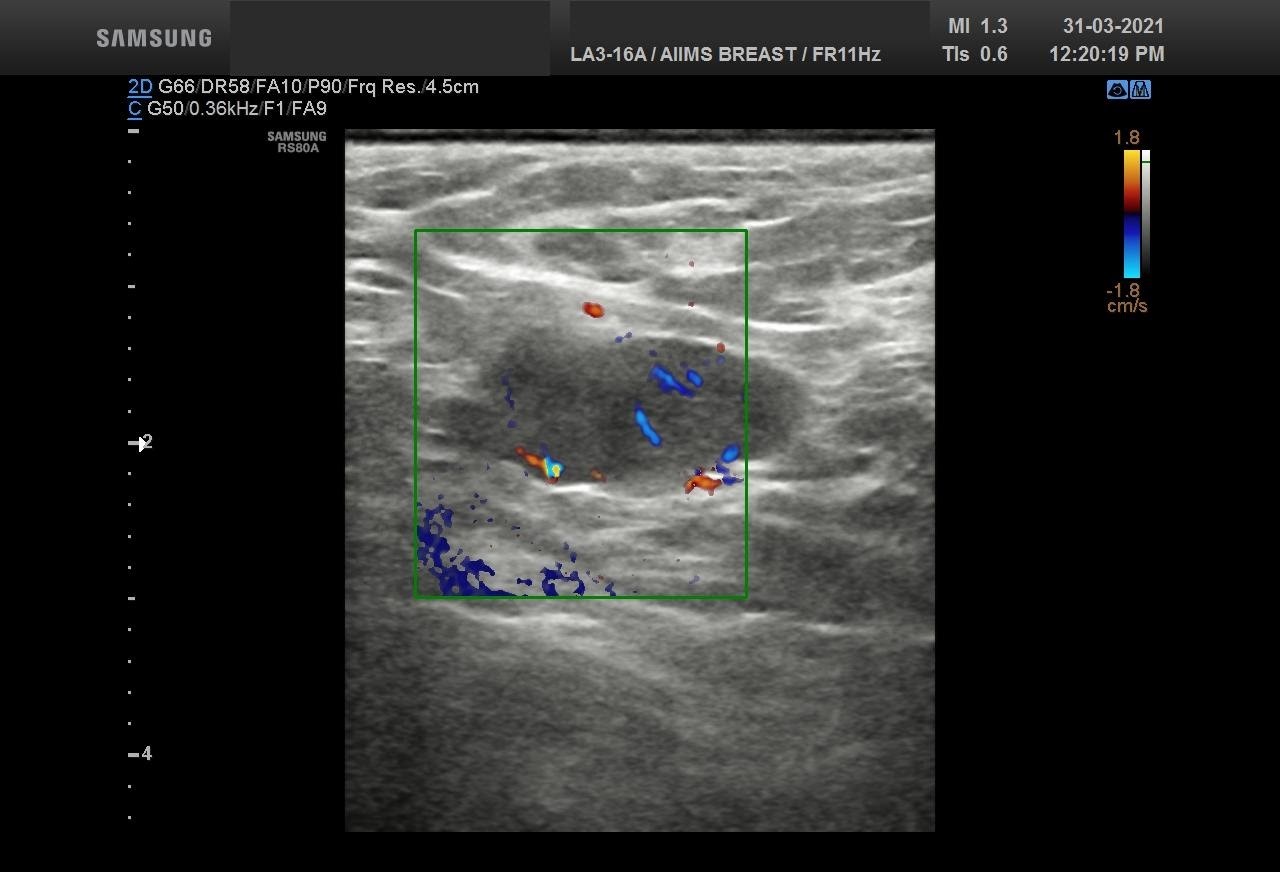

Bilateral Digital mammography , Craniocaudal (CC) and Mediolateral oblique (MLO) view with tomosynthesis images revealed a round shaped, equal density mass with indistinct margin in lower outer quadrant. No suspicious microcalcifications was seen. No significant axillary lymph nodes were present. A high resolution ultrasound of the right breast showed a round shaped, heterogeneously hypoechoic mass with irregular margin, small cystic spaces within and posterior acoustic enhancement, measuring about 1.6x1.9x1.5cm at 7 O’clock position. Mild internal vascularity was noted on colour doppler images. Right axilla showed suspicious lymph nodes with loss of fatty hilum and thickened cortex.